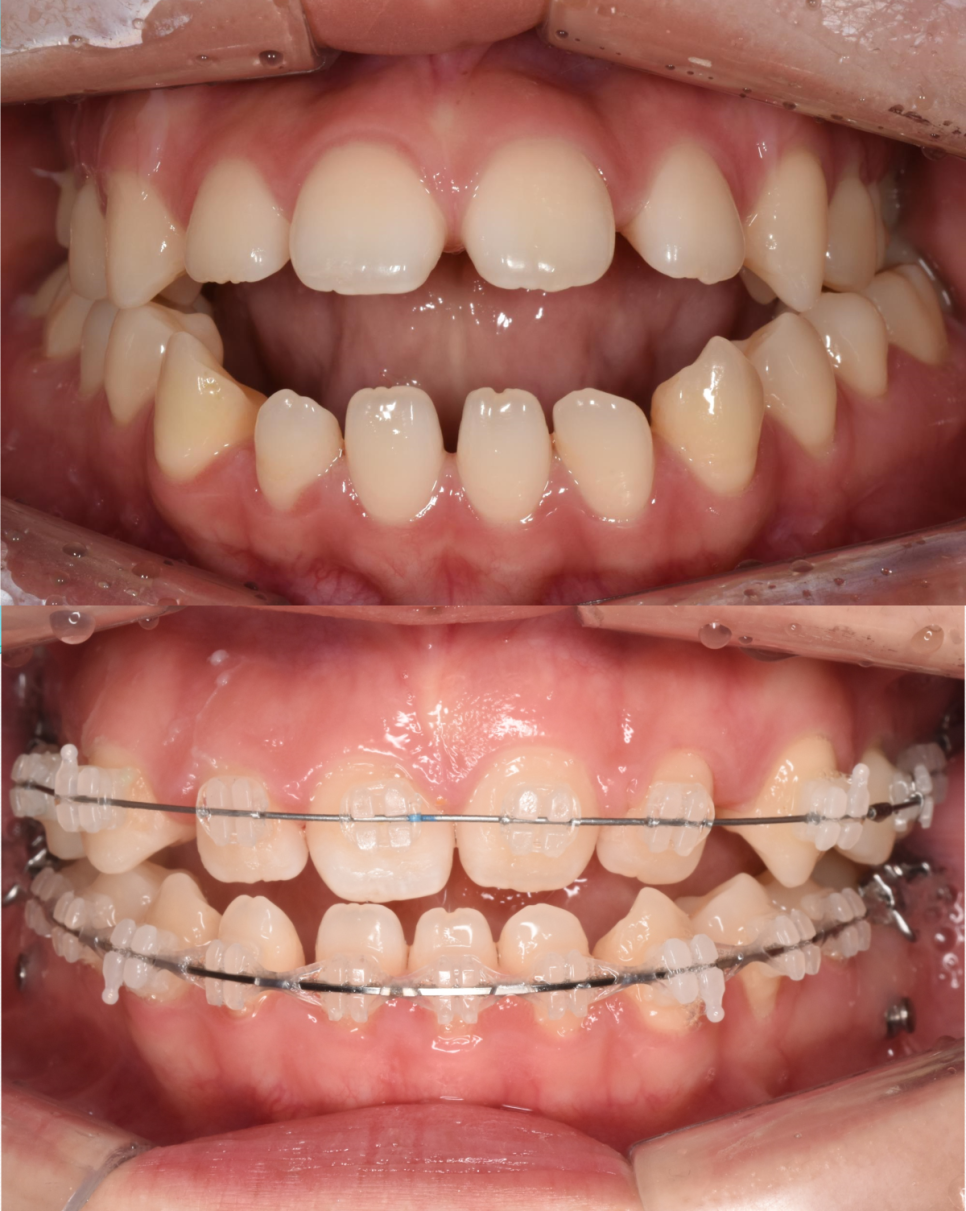

치료 전후 비교사진

치료 전 상태

20대 초반의 이 여성 환자분께서는 처음 내원하셨을 때 세 가지 큰 고민을 가지고 계셨습니다.

"앞니가 안 다물어져요"

"얼굴에 비대칭이 있어요"

"입을 넣고 싶어요"

환자분은 이미 대학병원까지 방문하셨던 상태였고, 그곳에서 이러한 골격적 문제들을 해결하려면 수술교정이 반드시 필요하다는 진단을 받으셨다고 합니다. 하지만 수술이라는 큰 과정을 앞두고 심리적인 부담감이 크셨고, 절실한 마음으로 수술 없는 대안을 찾기 위해 저희 치과를 찾아주셨습니다.

환자분께서 느끼시는 불편함은 세라믹치과의 정밀 검사 결과에서도 명확히 확인되었습니다. 어금니를 물어도 앞니가 다물어지지 않는 개방교합과 안면 비대칭, 그리고 미약한 돌출입 증상도 있었습니다.

구강 내부 상황도 복잡했습니다. 왼쪽 위 치아가 하나 결손된 상태였고, 그 공간 때문에 치아들이 전체적으로 벌어져 있었습니다. 대학병원에서 왜 수술을 권유했는지 충분히 이해가 갈 만큼 복합적인 문제들이 얽혀 있는 케이스였습니다.

(좌) 어금니가 다물어져있는데도 앞니는 물리지 않고 떠 있다. (우)환자분 기준 "왼쪽"에는 어금니가 하나밖에 없다

가장 먼저 진행한 작업은 좁았던 위턱을 양옆으로 시원하게 넓혀주는 것이었습니다. 위턱이 확장되면서 아래턱과의 너비 균형이 맞기 시작합니다. 전후 사진을 보시면 좁았던 아치가 완만한 곡선을 그리며 넓어진 확실한 차이를 확인하실 수 있습니다.

2단계: 교합 개선(맞물림 조정)

위턱의 틀이 확보된 후에는 위아래 어금니가 올바르게 물리도록 세밀하게 조정합니다. 사실 이 단계까지만으로도 많은 변화가 일어납니다. 혀가 제 자리를 찾으면서 밀려 나갔던 앞니 공간이 상당 부분 개선되고, 비정상적으로 높게 물리던 교합이 안정되면서 육안으로 보이는 턱의 길이도 훨씬 짧아 보이게 됩니다.

치료 결과

이렇게 모든 치료가 끝났습니다. 환자분의 처음 고민이었던 세 가지 문제가 어떻게 개선 되었는지 다시 한 번 정리해보겠습니다.

앞니 개방교합의 해소

좁았던 입천장이 넓어지자 갈 곳 없던 혀가 자연스럽게 제자리를 찾게 되었습니다. 혀가 앞니를 밀어내던 힘이 사라지면서, 붕 떠 있던 앞니들이 비로소 정상적으로 맞물리기 시작했습니다. 이제는 음식물을 앞니로 편하게 끊어 드실 수 있게 되었고, 미소도 훨씬 예뻐졌습니다.

돌출입 증상의 개선

치아들이 배열될 충분한 공간이 확보되자, 앞으로 뻗어 있던 치아들이 제 위치로 들어갔습니다. 이 과정에서 입술 라인이 자연스럽게 뒤로 이동하며, 환자분이 원하셨던 세련되고 편안한 입매가 완성되었습니다.